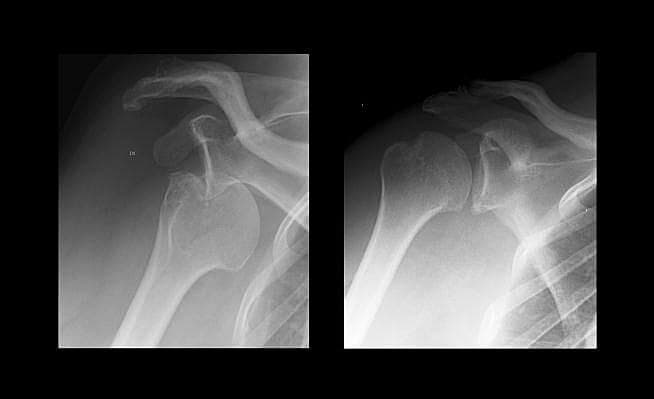

En 56-årig mand kom til skadestuen efter et fald på 1,5 meter fra en fiskerbåd og ned på en havnekaj. Den første røntgenoptagelse (til venstre) viste en anterior luksation af højre skulderled, hvor den posterolaterale del af caput humeri var presset op i labrum glenoidale og fastlåst i denne stilling. Forsøg på reponering i let sedation og intraartikulær analgesi var uden succes, og luksationen blev derfor reponeret i generel anæstesi.

Det unikke ved billedet til venstre er, at det særlig tydeligt viser de mekaniske kræfters virkning i det traume, der danner den såkaldte Hill-Sachs-læsion. Hill-Sachs-læsionen er en impression i caput humeri efter luksation af humeroscapulærleddet og ses tydeligt på kontrolbilledet til højre, der blev taget efter repositionen.

Hill-Sachs-læsionen blev første gang beskrevet i 1940 af to amerikanske røntgenlæger [1], og patienter med denne læsion har forhøjet risiko for ny luksation.